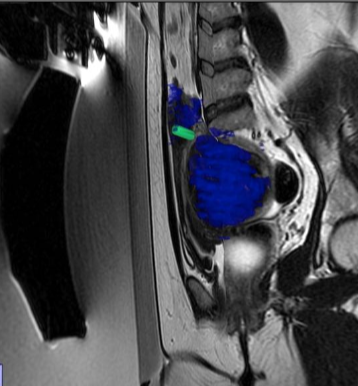

在开始该程序之前,会先进行手动分割操作。 随后,一款专用软件会自动制定出最佳的治疗方案。

在操作过程中,会进行多次超声波治疗,直至覆盖住足够的子宫肌瘤体积。 每次超声处理持续 20 至 40 秒,每次超声处理之间会有冷却时间(最长可达 90 秒)。 磁共振成像技术中质子共振频率的偏移特性使得能够监测每一个治疗点的温度。

经过治疗后,会进行核磁增强以评估被切除区域的范围。

因子宫肌瘤接受磁共振聚焦超声治疗的患者的治疗前后 CE-T1W 磁共振成像图像。 治疗结束后立即进行增强型磁共振成像检查,结果显示存在未灌注区域。

消融区域坏死周边,残留的部分好像不少,会不会是MRgFUS 再干预机会大的原因